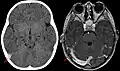

Wegen dieser Schwierigkeiten wird bei entsprechendem Verdacht frühzeitig eine Schnittbilddiagnostik des Schädels empfohlen. In der Computertomographie oder Kernspintomographie sind Infarktzonen und Blutungen erkennbar, die nicht den bekannten arteriellen Versorgungsgebieten entsprechen. In der nativen Computertomographie (ohne Kontrastmittel) kann sich das Gerinnsel im Sinus hell, also dichter als das umliegende Gewebe (hyperdens), darstellen. Mit Kontrastmittel lassen sich sowohl in der Computertomographie wie auch in der Kernspintomographie die Gerinnsel direkt als Aussparung in den ansonsten kontrastierten Sinus meist gut erkennen. Die Diagnose kann gelegentlich schon im CT gestellt werden. In der Regel ist aber eine CT-Angiographie oder Kernspintomographie erforderlich. Mittel der Wahl zur Diagnostik von Venen- und Sinusthrombosen ist die Kernspintomographie, sie ist aber nicht immer verfügbar. Die Kernspintomographie sollte auch suszeptibilitätsgewichtete Bilder und eine Time-of-flight-Angiographie enthalten, um alle Thrombosen zu erfassen.[23] Die interventionelle Angiografie mit einem Katheter kommt nur noch in Ausnahmefällen in Betracht und spielt im deutschsprachigen Raum fast keine Rolle mehr.[2] Bei Neugeborenen wird die Ultraschalluntersuchung des Gehirns über die Fontanelle vorgezogen.[5]